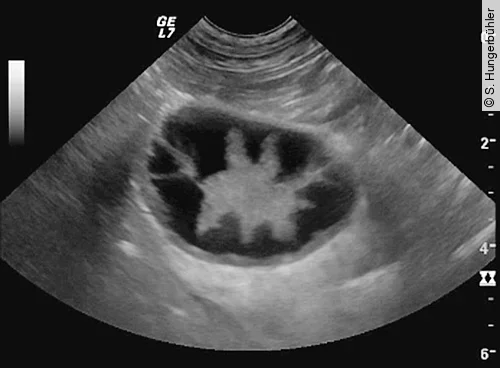

Das Kiwi-Stadium (Abb. 4) ist dagegen vor allem durch die hochgradig verdickte und auffällig lamellierte Wand und zentral gelegenem echogenem Sludge charakterisiert [8]. Das Stern- und Kiwi-Stadium sind verschiedene, voneinander unabhängige Manifestationen einer MZ.